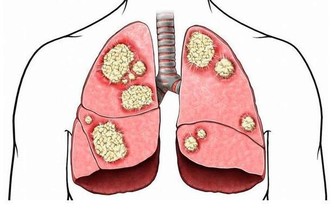

據統計,約有22%的素食者會得脂肪肝,而這些人也大多是正常體型。劉曉光醫師稱,人體中所需要的能量主要來自三大營養物質,脂肪、蛋白質和碳水化合物。像陳先生這種純素食者,不吃魚肉蛋等營養物質,也就是少了動物蛋白質和脂肪來源,人體的白蛋白合成減少,就需要分解脂肪組織來維持營養均衡,大量的脂肪酸從脂肪組織中釋放進入肝臟后,而這種脂肪在肝臟中不易被分解,若不能及時排出,肝臟中的脂肪堆積過多,長期以往,就形成了脂肪肝。

不只是素食主義者有患病隱患,曾經有社區在湖北武漢對歸元寺、鐵佛寺的兩寺僧人進行體檢,結果令人大吃一驚:受檢的30名僧人中,接近一半的僧人的肝內總脂肪量佔到肝重的5%-10%,達到輕度脂肪肝的標準。

脂肪肝已成為人類第一大肝病

目前,世界各地的脂肪肝的發病率逐年上升,發病年齡也越來越小。它可能發生於各個年齡段,以40-50歲最為常見。酒精性脂肪肝男性患者居多,非酒精性脂肪肝過去認為以女性為主,近年來認為男女發病率幾乎相當。在發達城市,成人脂肪肝的患病率更是超過了30%,主要病因就是營養過剩和酗酒,所以脂肪肝又被稱為「富貴病」。而在一些貧窮地區,由於蛋白質、熱量攝入不足也會引起脂肪肝。通過上文所知,脂肪肝不只是胖子的專利,瘦人也可發生。